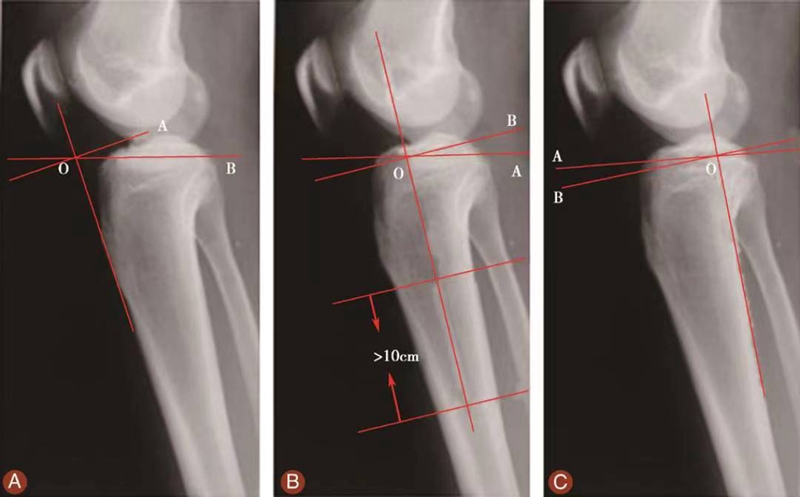

测量胫骨后倾角时先要观察胫骨上段及其与腓骨的位置关系,选择无明显胫骨旋转的,胫骨平台轮廓清晰的膝关节X侧位片。方法1测得的胫骨后倾角范围是11.74°±3.87°,方法2测得的胫骨后倾角范围是8.91°±3.57°,方法3测得的胫骨后倾角范围是6.21°±3.51°。

图15 胫骨后倾角的评估

用量角器测量胫骨内侧平台前后缘连线分别与胫骨中上段前侧骨皮质切线的垂线(图15A)、胫骨结节下胫骨中上段轴线的垂线(图15B)以及胫骨后侧皮质切线的垂线(图15C)的夹角,即胫骨后倾角(∠AOB)